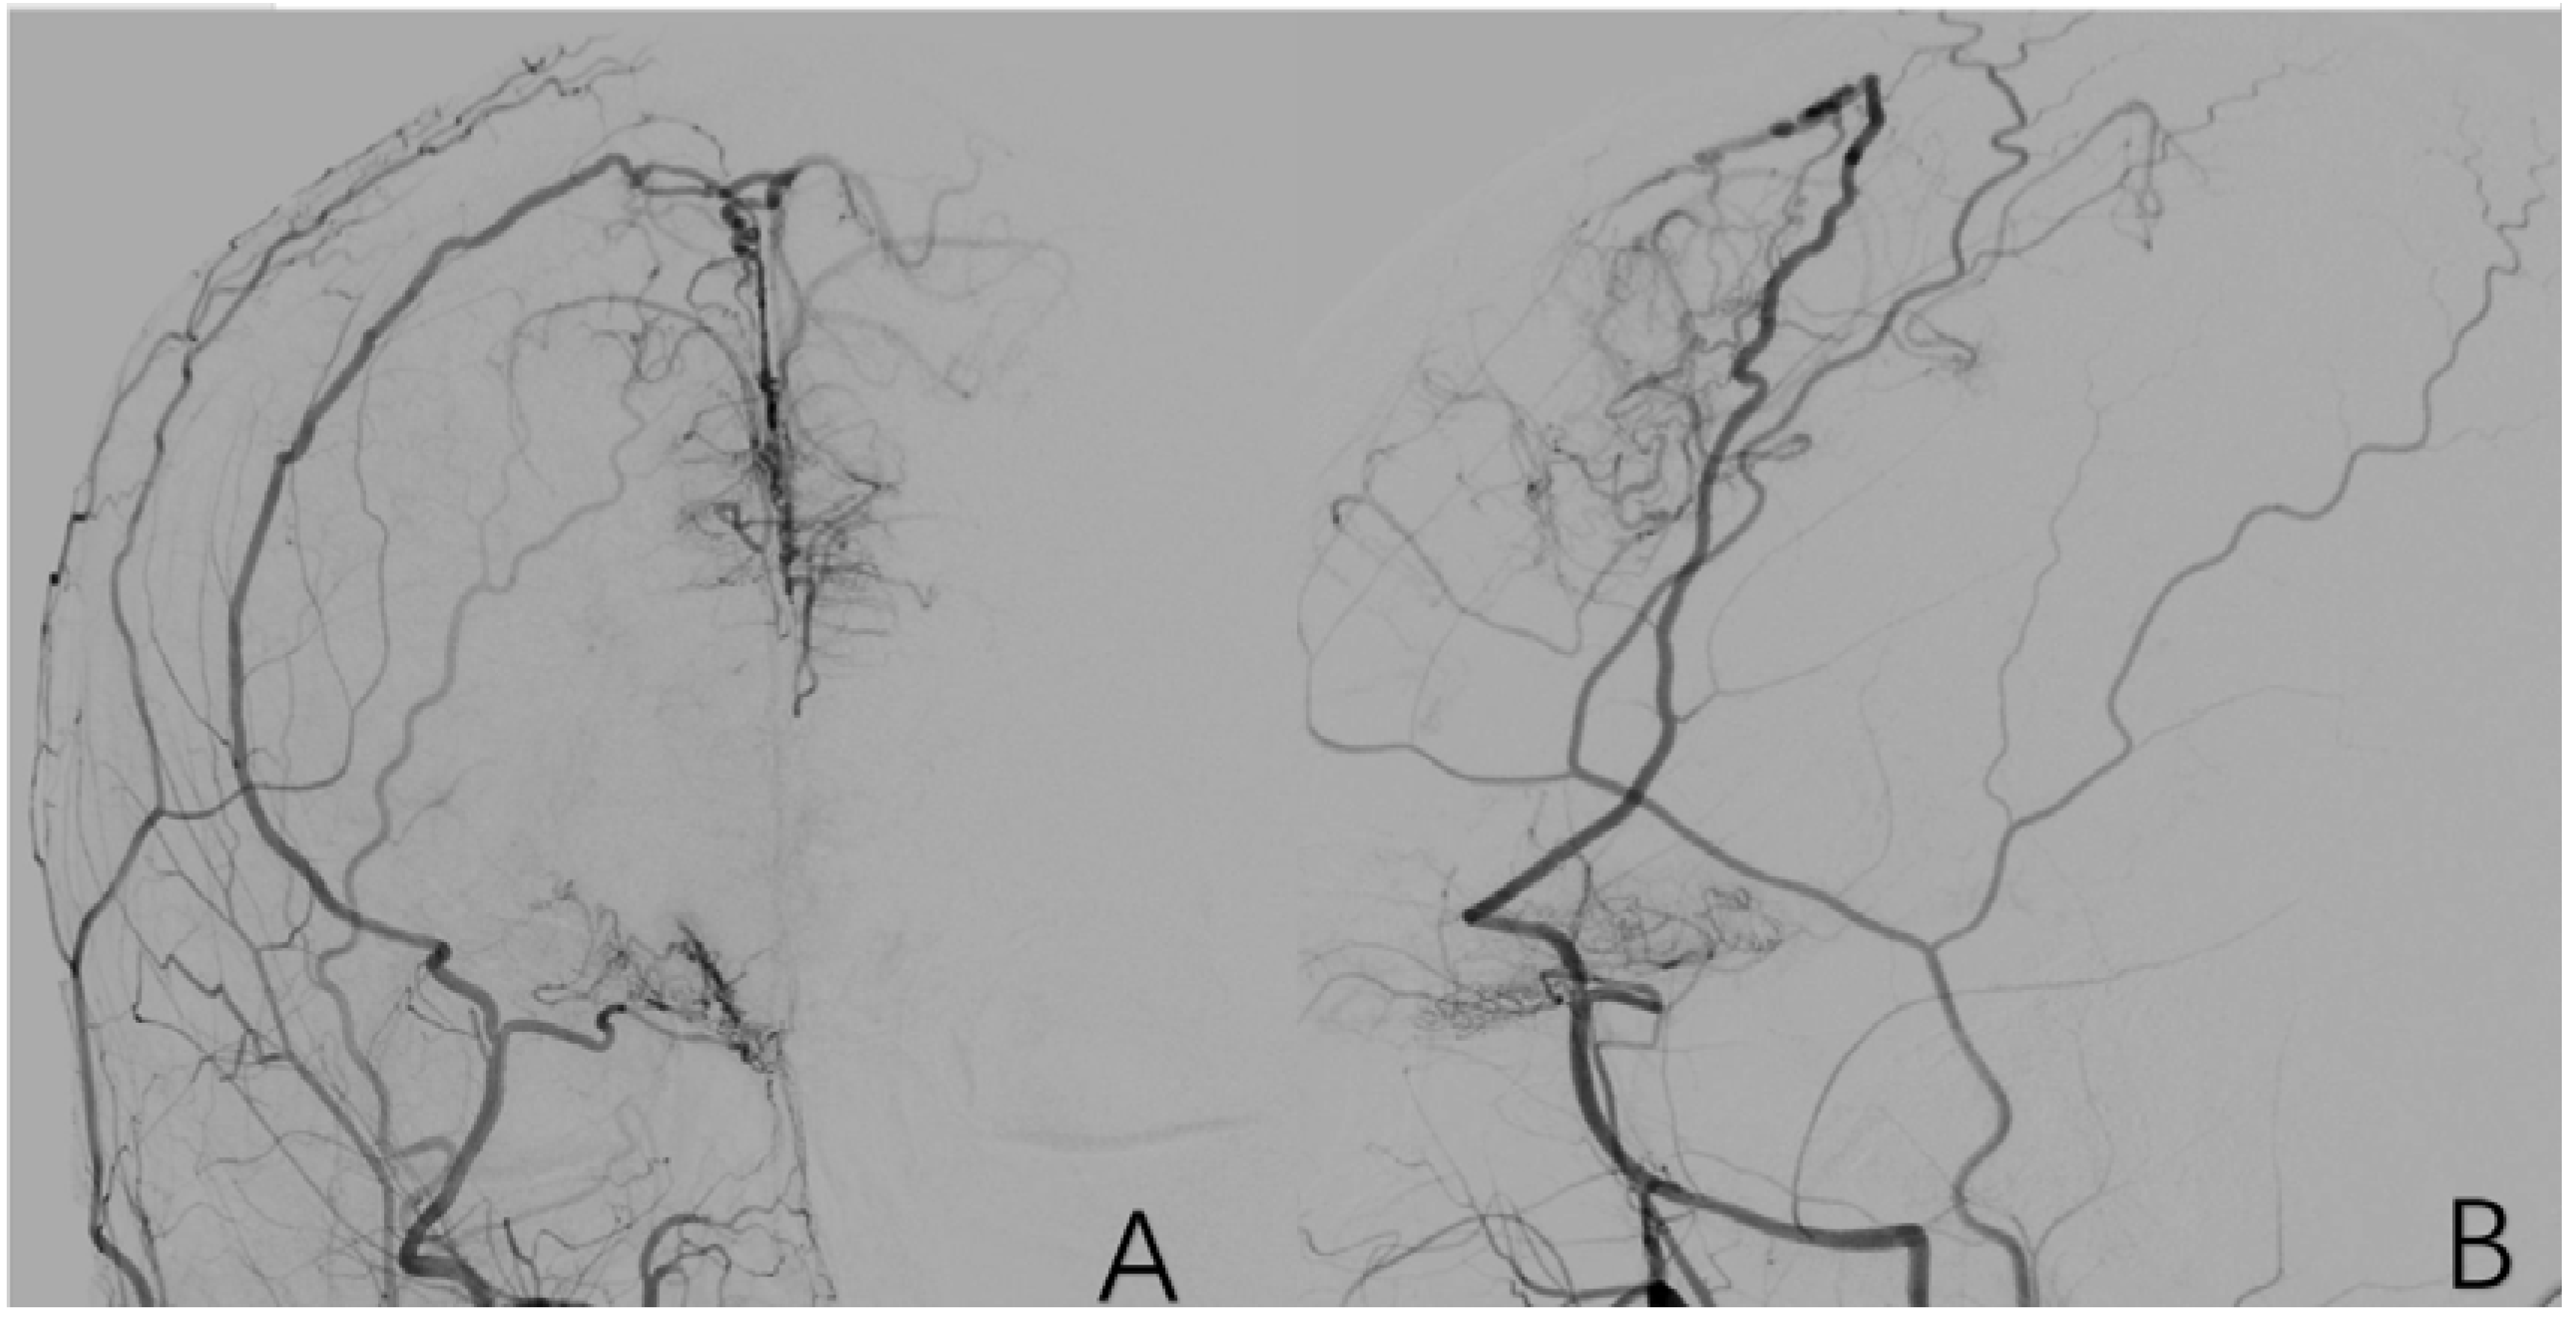

2.3.9. Factor 4 PCA Anomaly

2.3.10. Factor 5 Posterior Circulation Compensation